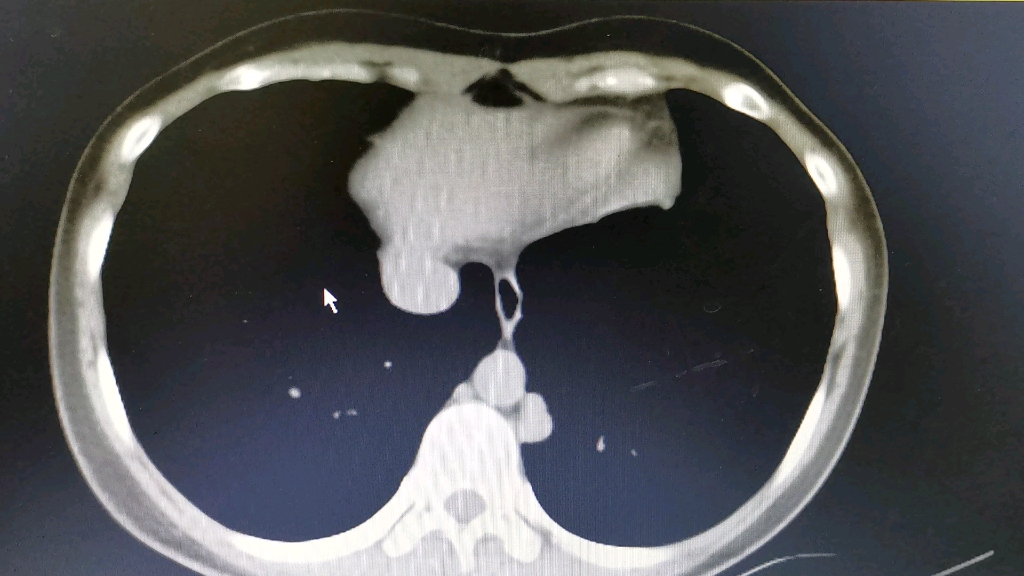

中年女性头晕入院ct发现胸膜多发结节请分析有结果